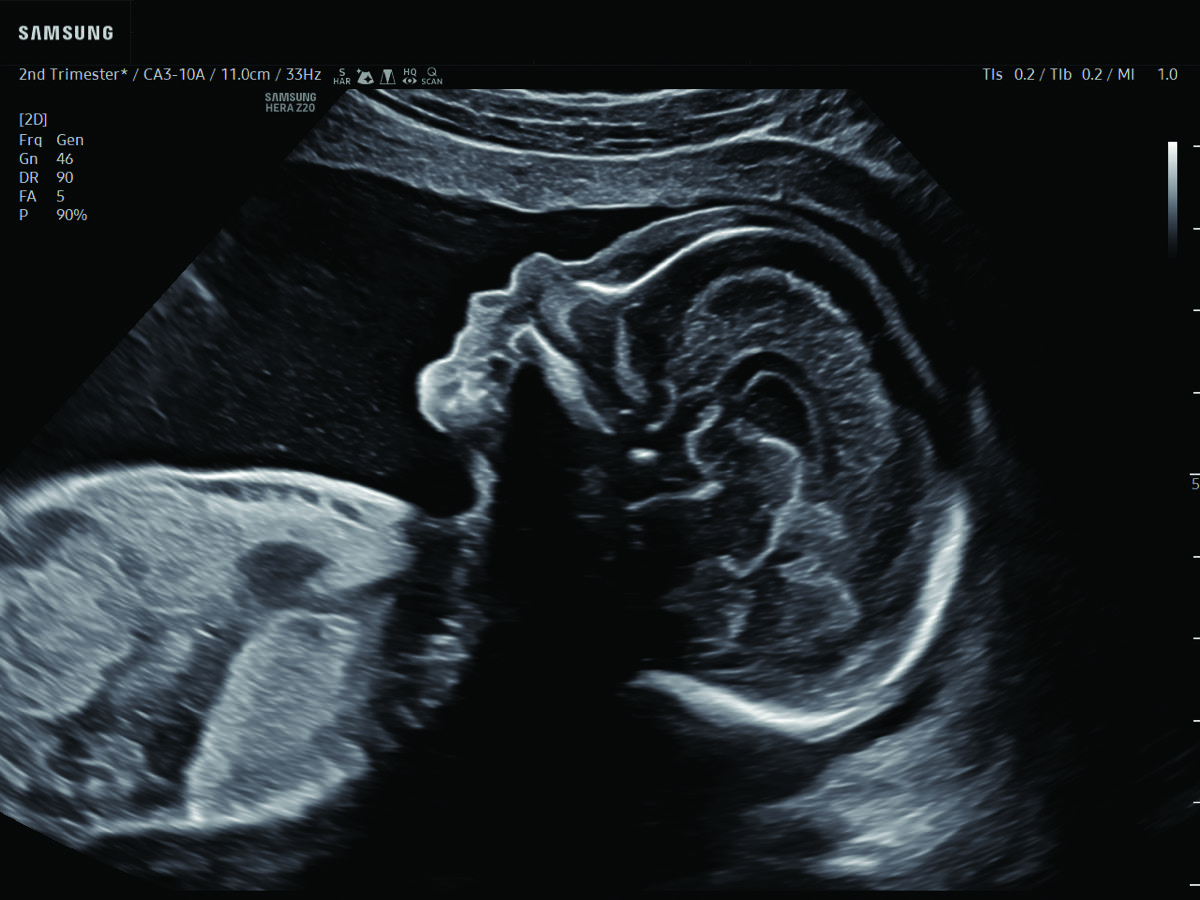

Comprehensive, advanced and expert MFM care for high-risk pregnancies

- Fetal anomalies

In-depth evaluation of maternal and fetal conditions requiring specialized care such as diabetes, hypertension, thyroid disease, autoimmune disorders, or fetal growth or anatomy concerns.